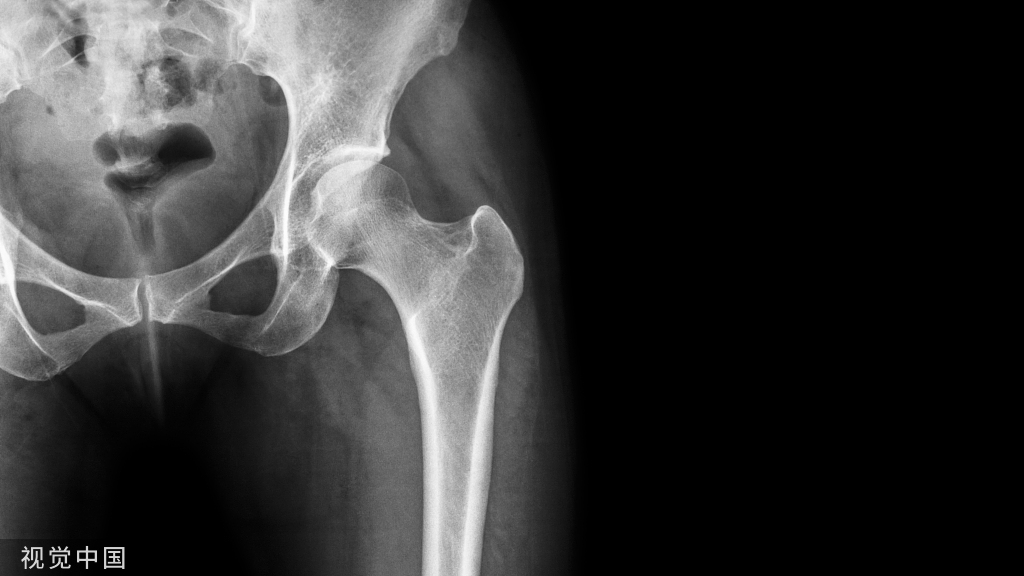

内固定术是用金属螺钉、接骨板、髓内针、钢丝、钛缆或骨板等物直接在骨内或骨外将骨折、关节或脊柱连接固定起来的手术。

内固定物的作用是为了维持稳定,如骨折对位对线后,使用内固定物维持对位对线并固定牢固;又如关节融合手术,为了维持准备融合关节的稳定以便关节融合,需要相应固定材料进行固定;还比如脊柱退变手术,为了维持脊柱的稳定,避免出现或者为了纠正脊柱不稳,也需要内固定来维系。因此,在骨科很多手术中,进行内固定术是必不可少的。

一旦骨折愈合、脊柱融合、关节融合等,内固定物就完成了使命,也就是说内固定物“没用”了,再加上内固定物材料大多系金属材质(目前有些内固定物是可吸收材料,不在我们这次的讨论范围),对人体来说总归是异物。因此,大多数人都认为这时内固定物就应该取出来了。